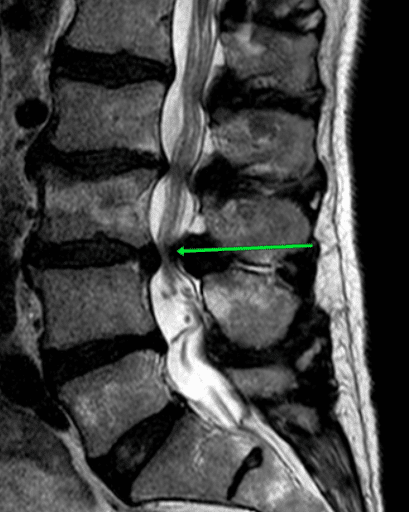

Przed operacją zwężenie kanału może być widoczne na obrazach diagnostycznych, takich jak rezonans magnetyczny. Przerośnięte więzadła oraz uwypuklenia krążków międzykręgowych ograniczają przestrzeń dla struktur nerwowych, powodując ból oraz zaburzenia neurologiczne.

Strzałka wskazuje przerośnięte więzadło żółte, które zwęża kanał kręgowy pomiędzy kręgami L3 i L4.